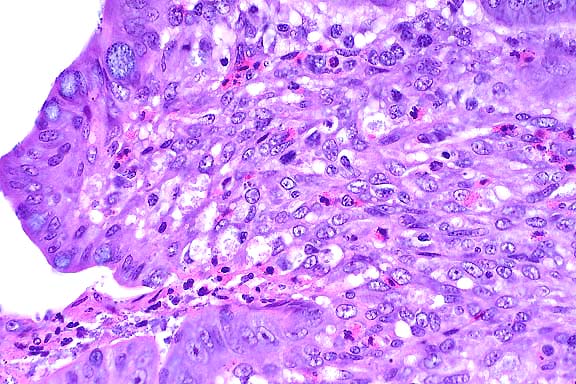

- Contributor's Diagnoses and Comments:

- 1. Testicle: Interstitial cell tumor, with multifocal infarction.

- 2. Testicle: Moderate to severe diffuse atrophy of seminiferous

tubular epithelium, multifocal mineralized intratubular debris

and occasional spermatozoa.

- 3. Omentum: Metastatic interstitial cell tumor.

-

- Interstitial cell tumors (ICT) are derived from Leydig cells

and rarely metastasize. A continuum was noted from a less well

differentiated cell type which had a hyperchromatic central round

nucleus and a modest amount of a lightly basophilic cytoplasm,

to larger round polyhedral cells with abundant lightly eosinophilic

to vacuolated cytoplasm in the more well differentiated cells.

There was mild cytomorphologic atypia and a slightly higher mitotic

rate (2-4/hpf) in well differentiated areas of the tumor. The

sharply demarcated focus of tumor necrosis is suggestive of vascular

compromise due to possible tumor emboli. Numerous tumor metastases

were noted in the omentum. The mineralized debris in the seminiferous

tubules appeared to obstruct flow, trapping the few spermatozoa

present in the nearby tubules resulting in mild distention.

- Case 16-4. Testis, Epididymis. Replacing seminiferous

tubules and extending around adjacent epididymal tubules, there

is an expansile, infiltrative mass consisting of sheets of polygonal

cells bearing pale granular, often vacuolated cells with oval

to round nuclei with granular basophilic chromatin.

- AFIP Diagnoses:

- 1. Testis: Interstitial cell tumor, malignant, hedgehog,

insectivore.

- 2. Adipose tissue (omentum per contributor): Interstitial

cell tumor, malignant, metastatic.

- Conference Note: A densely cellular neoplasm has effaced

the testis and infiltrated the epididymis. It is composed of

polygonal cells arranged in broad cords, nests, packets and solidly

cellular areas, supported by a fine fibrovascular stroma. In

some areas, neoplastic cells palisade along the vascular stroma.

Neoplastic cells have indistinct cell borders, moderate amounts

of eosinophilic cytoplasm, and oval to elongate nuclei. Some

polygonal cells contain very distinct, clear, cytoplasmic vacuoles.

The mitotic rate is high, and some mitotic figures are bizarre.

Similar neoplastic cells are found within the submitted sections

of mesentery. Based on histomorphology, conference participants

agreed with the contributor's diagnosis. The differential diagnosis

that was considered included seminoma, Sertoli cell tumor, lymphoma,

mast cell tumor, and mesothelioma.